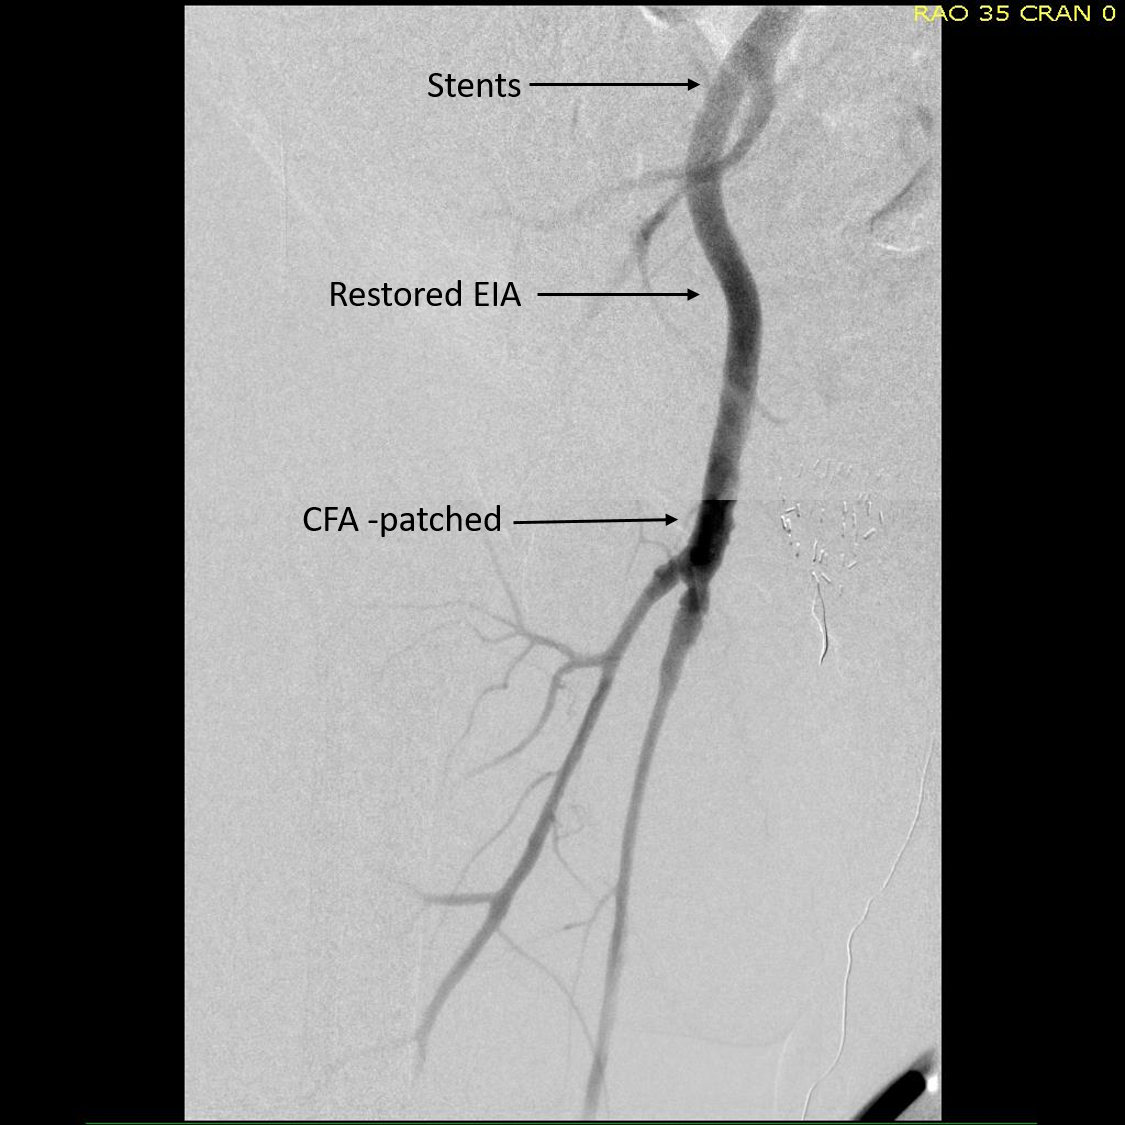

The patient is an active man in his 60’s with a history of hypertension who had known about a right common iliac artery aneurysm for several years and had come for an opinion. He was asymptomatic of pain. He had a prior splenic artery aneurysm embolization about a decade prior to presentation.. CT scan showed a large eccentric aneurysm arising from a retrograde chronic dissection dilating the right common iliac artery to over 4cm. This is typically iatrogenic, but impossible to know for sure. The left common iliac artery was ectatic to 2cm as was the aorta to 3 cm and all were “wavy.” This sort of tortuosity is the result of remodeling in the axis of flow resulting in lengthening of the artery and is found in those with the substrate for aneurysmal degeneration (footnote). He did not smoke and he could climb stairs without dyspnea or chest pain.

abd angio  1605093750..jpg

On examination, he was a fit middle aged man with a slight paunch. His abdomen was soft and his peripheral pulses were present and normal. Laboratory results were normal, including creatinine. EKG and echocardiogram were also normal.Treatment options were discussed in detail. The patient was paying for the operation himself and wanted to understand in detail the possible options. These included

We chose open surgical repair via a midline laparotomy. An aortobi-iliac bypass was performed from proximal aorta to right internal iliac artery and left common iliac artery bifurcation with a jump bypass from the right graft branch to the right external iliac artery. Technically, this sequence was chosen for ease of access to the internal iliac artery with the external clear of graft. Operative time was 3 hours. He was in the ICU for one night. He went home after 10 days after contracting a UTI. In followup three weeks after discharge, because he had fevers, a CT scan was performed (figure). He was treated for an upper respiratory infection which cleared, and he has been doing well since. We are both happy that he will never need a followup CT scan.

Before and After